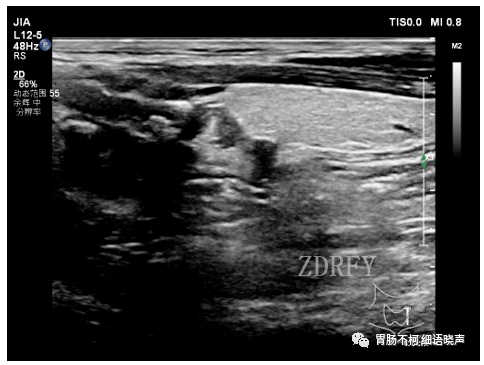

病例一:甲状腺左叶后方低回声型咽食管Killian-Jamieson憩室。

其后方与食管相通。

吞咽口水实验可见团块状强回声涌入。